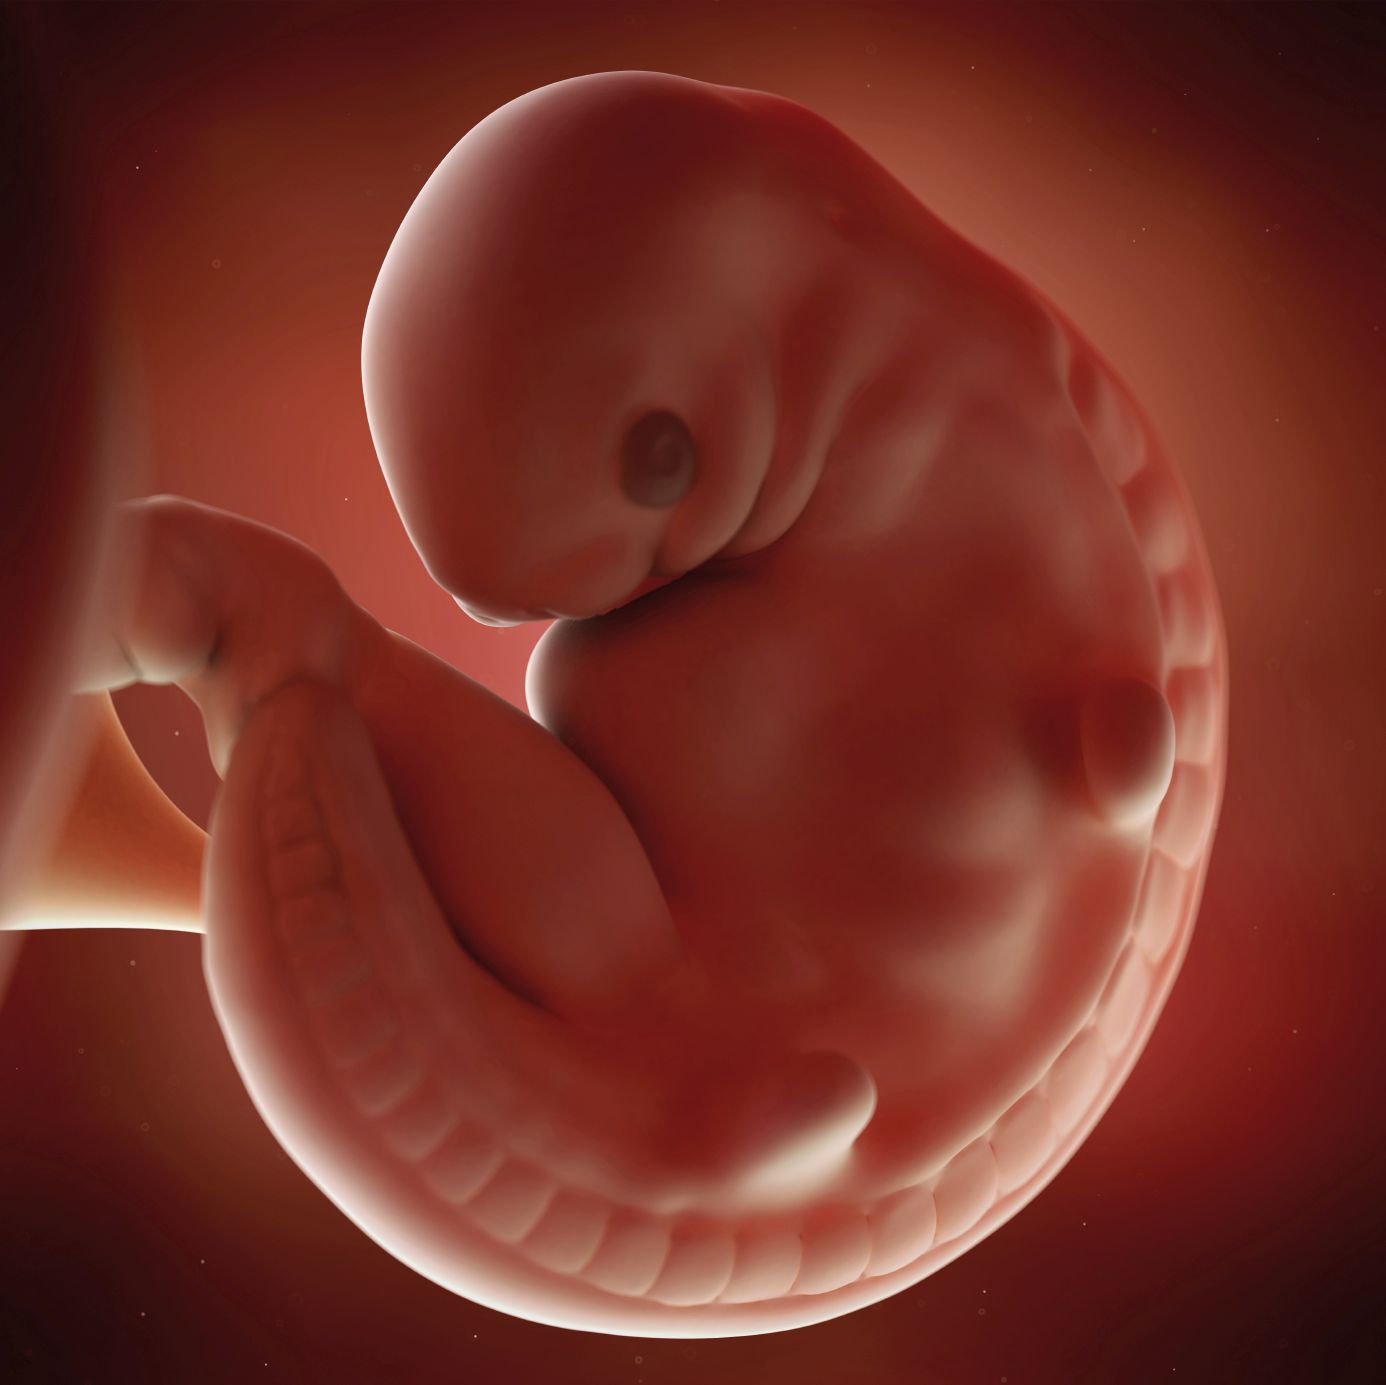

Pin On Fetus

Pin On Fetus

Fetal Development Middlesex London Health Unit

Fetal Development Middlesex London Health Unit